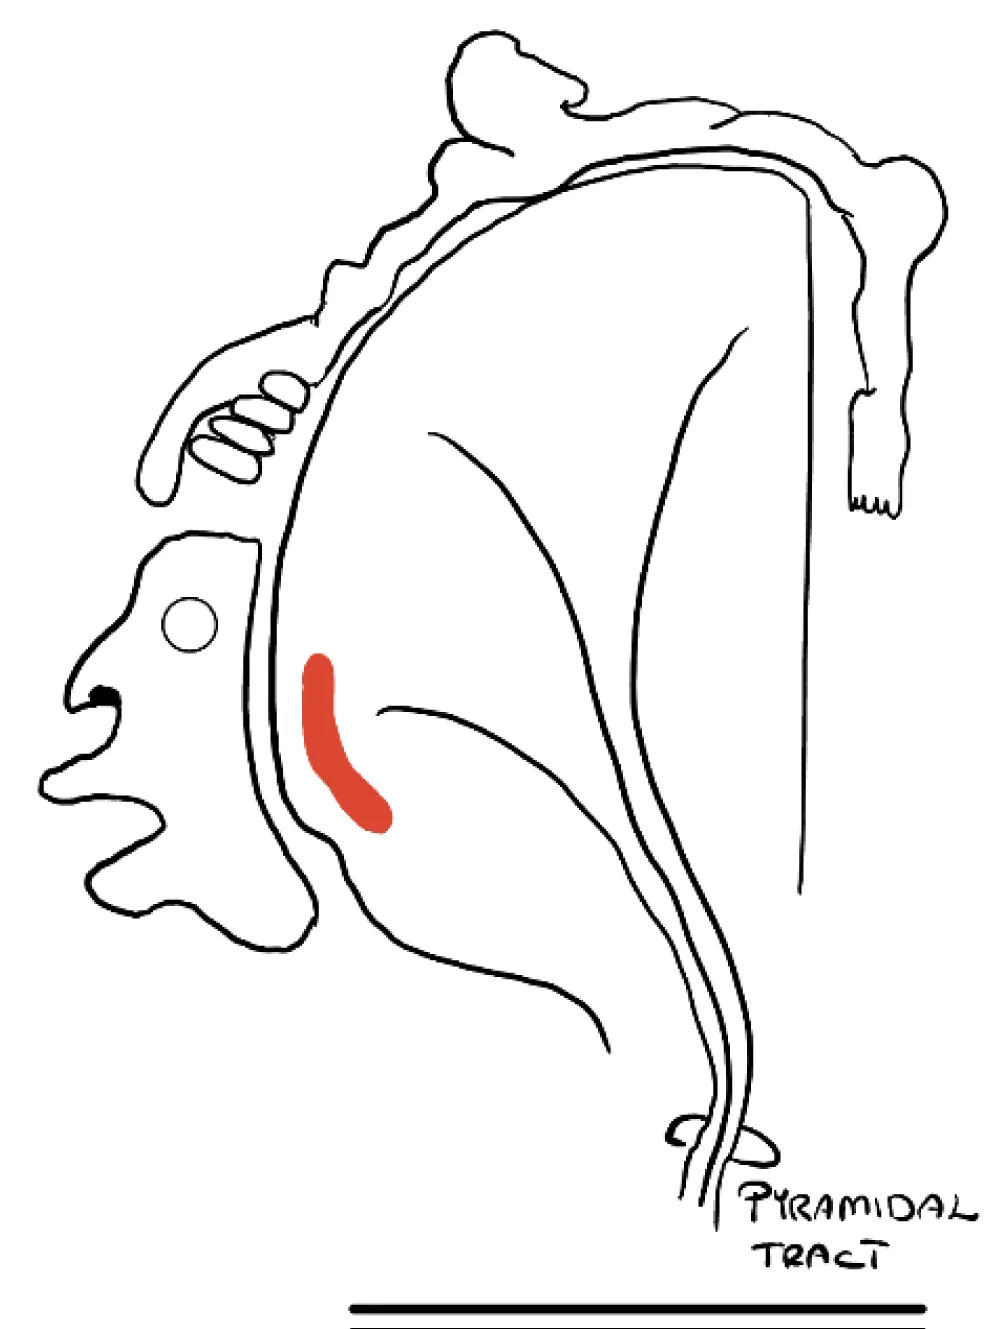

Laryngeal Motor Cortex (LMC) (Figures 3,4)

Figure 3: The laryngeal motor cortex as marked in red comprises a significant part of the human motor homunculus.

Figure 4: Corticonuclear innervation of nucleus ambigus is bilateral but can be unequally represented. The left side has rostral and caudal LMC areas which innervate the Nucleus ambiguus bilaterally while the right side only has rostral LMC innervating bilateral nuclei. Lesions affecting Left LMC centers and/or its projection to the nuclei may have a profound effect on the weakness of the vocal cord compared to similar lesions on the right side. LMC = Laryngeal Motor Cortex.

Recent work suggests that humans have two LMCs. The rostral LMC in the premotor cortex is phylogenetically and ontogenetically ‘old’. It is involved in the control of innate behaviors. The caudal LMC in the primary motor cortex is phylogenetically ‘newer’ and is involved in the control of learned behavior, especially speech. [3] argues that humans have only a ‘new’ LMC on the right, but both ‘old’ and ‘new’ LMCs on the left. This asymmetry might explain the unexpected finding of a unilateral (left) cerebral lesion causing VC paralysis in our patient.

We are familiar with the hypophonia and abnormalities of VC control in patients with Parkinson’s disease. Focal lesions of the lentiform nuclei can cause hypophonia [4,5]. [6] report a case of bilateral putaminal infarcts causing aphonia. Simonyan, et al. 2014 [3] also report bilateral lentiform nuclei changes in spasmodic dysphonia. We speculate that the lesion disrupted cortico-striato-pallido-thalamic-cortical circuitry, and that, because of the asymmetric organization of the LMC, this resulted in bilateral VC palsy.